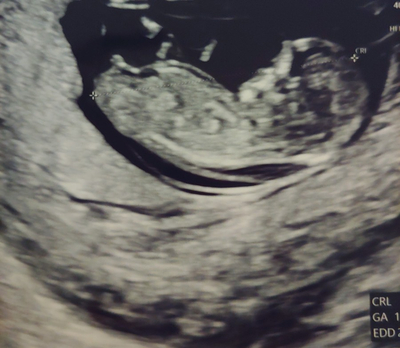

1. 1차 정밀초음파&통합선별검사 임신 12주는 중요한 시기로 아이가 많이 성장하여 배아초음파가 가능해져 1차 정밀초음파검사와 통합선별검사를 실시합니다.

2. 정밀 초음파는 1차(10~13주), 2차(20~21주)에 진행되는데, 1차 정밀 초음파 검사: 태아목 투명대(NT) 두께 측정으로 태아의 염색체, 심장에 이상이 있는지 확인합니다.보통 2.5mm 미만이 정상입니다.(목 투명대란, 아기를 둘러싼 양막에서 목까지의 빈 부분입니다.)

2차 정밀 초음파 검사: 태아의 성장(외형, 내부 장기 등)을 파악합니다.분만일 기준 만 35세 이상 산모, 이전에 염색체 이상이 있는 아이를 임신한 산모 등 위험군이 아니라면 보통 통합 선별검사, 1차 2차 산모의 혈액검사를 통해 다운증후군 등 이상 여부를 파악합니다.하지만 직접적인 태아의 염색체를 확인하는 방법이 아니기 때문에 진단률은 90~94%로 진단을 놓칠 가능성이 5~10%가 됩니다.